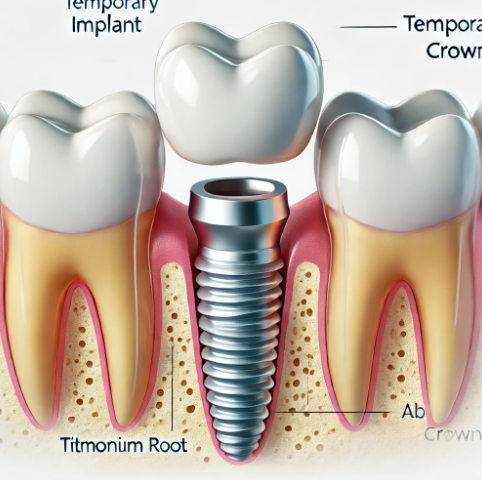

원데이 임플란트에 대해 찾으셨나요? 그래서 오늘 원데이 임플란트 비용 및 가격, 조건, 추천 대상 들에 대해 살펴보겠습니다. 오늘 내용을 확인하시면 원데이가 어떤 차이점을 가지고 있는지, 어느 대상에게 적합한지, 가격 및 장단점 등에 대해서 정리가 되실 것입니다. 하기를 참고해주세요. 근처 임플란트 가격 조회 🔍 원데이 임플란트 원데이 임플란트는 이름 그대로 하루 만에 임플란트 시술이 … Read more